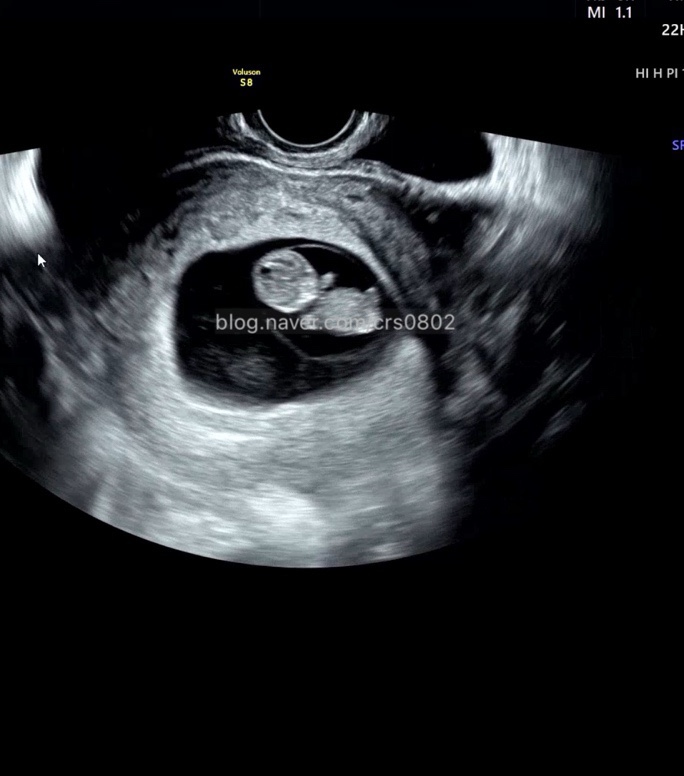

둘째기록_ 현대해상 태아보험, 어린이 종합보험 가입 (10년납 30세만기)

첫째때도 가입한 태아보험 되게 느릿느릿 가입했다고 들었는데... 생각해보니? 첫째도 15주4일에 들었던 태...

세명에서 네명으로! 임밍아웃

아직 공공연하게 알리지는 못했고... 주변 친하게지내는 사람들은 이미 알고있지만!!!! 12주가 지났으니? ...